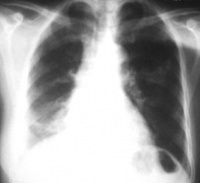

肺炎

肺炎支原体(M.Pneumonia)是人类支原体肺炎的病原体。支原体肺炎的病理改变以间质性肺炎为主,有时并发支气管肺炎,称为原发性非典型性肺炎。主要经飞沫传染,潜伏期2~3周,发病率以青少年最高。临床症状较轻,甚至根本无症状,若有也只是头痛咽痛发热咳嗽等一般的呼吸道症状,但也有个别死亡报道。一年四季均可发生,但多在秋冬时节。